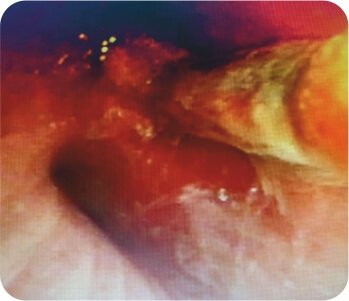

CT chest was suggestive of cavity in left upper lobe. FOB was suggestive of pus oozing from left upper lobe bronchus with a clot mass adherent to left upper lobe bronchus. Subsequent bronchoalveolar lavage was predominantly neutrophilic. Staining and culture for pyogenic, fungus, tuberculosis and nocardia was negative. Cytology was negative for malignancy. A diagnosis of Invasive Mucormycosis was made.

Rigid bronchoscopy + Cryobiopsy of protruding mass + Endobronchial blocker ( Fogarty balloon) was done.

Cryobiopsy of the protruding mass suggestive of invasive mucor mycosis (Broad aseptate hyphae)